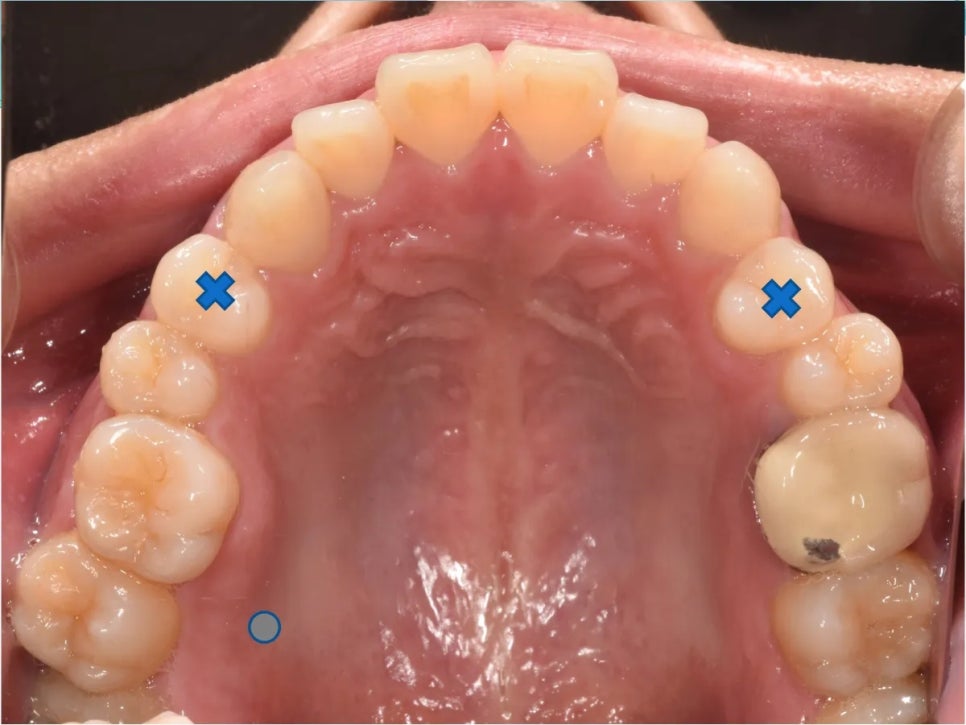

그런데 검진을 시작하자마자, 돌출입 외에도 여러 가지 문제들이 눈에 들어왔습니다. 오른쪽이 아예 물리지 않는 교합 불량, 어금니가 비정상적으로 내려온 상태(정출), 위아래 앞니가 너무 깊게 물리는 과개교합, 심한 충치, 그리고 이미 빠져 있는 치아까지. 단순 돌출입 교정이 아닌, 종합적인 교정 치료가 반드시 필요한 케이스였습니다.

위 어금니가 내려와있어서(노랑), 오른쪽은 이가 안 물리고 있고(빨강), 당연히 앞니의 중심선도 안맞습니다(파랑).

| 위 오른쪽 첫 번째 작은어금니 | 돌출입 개선을 위한 공간 확보 |

| 위 왼쪽 첫 번째 작은어금니 | 돌출입 개선을 위한 공간 확보 |